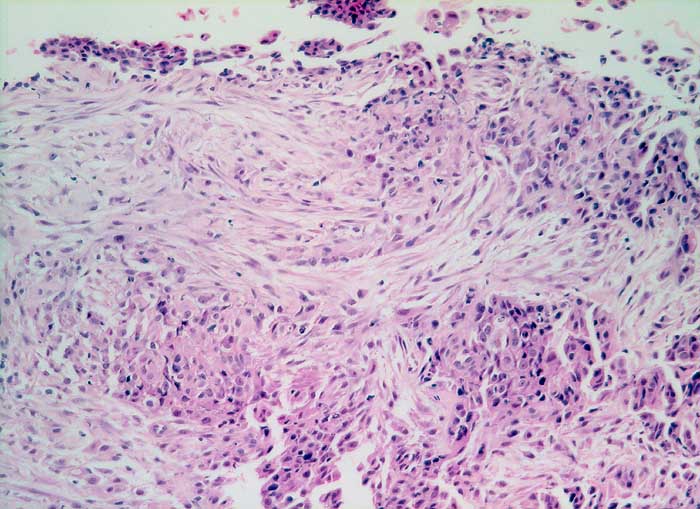

PathoPic – image database / PathoPic ID 5894 - malignes Pleuramesotheliom Mischtyp

malignes Pleuramesotheliom Mischtyp

Der Tumor besteht aus einer sarkomatoiden spindelzelligen Komponente und einer überwiegend soliden epithelialen Komponente aus kubischen Zellen mit hyperchromatischen Kernen.

Histologie

160